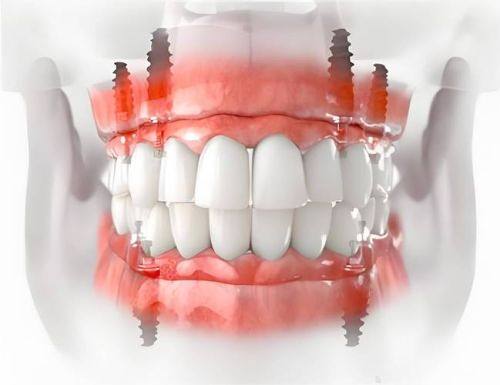

医院的设备也十分精良,引进了国内外精良的口腔诊疗设备,如数字化口腔全景机、种植机等,这些设备能够为患者提供更精细的诊断和更有效的治疗。而且医院的环境舒适宜人,采用了现代化的装修风格,让患者在就诊过程中感受到轻松和舒适。

丽水亮贝美口腔门诊部不仅实力强,而且性价比高。医院经常会推出一些优惠活动,让患者能够以更实惠的价格享受到优质的口腔治疗。例如,医院曾推出种牙3980元的活动,吸引了众多缺牙患者的关注。